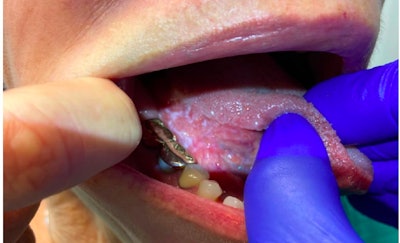

The rates of conversion of oral leukoplakia to invasive cancer is variable and cited to range from 0.13%-34%.5,6 Importantly, oral leukoplakia progressing to cancer remains infrequent, with many studies citing a < 1% risk of progression to malignancy over five to ten year periods. 6 Given variable malignant transformation rates, predictive factors for malignant transformation are poorly understood. For example, it is hypothesized, that specific risk factors for progression of oral leukoplakia to malignancy include patient symptoms, higher dysplasia grades, age, smoking status, and comorbidities.8,9 Physical exam findings hypothesized to increase risk of malignancy include nodularity, friability, multiple abnormal sites, lesion location on the tongue, and mass effect.9,10

We recently completed a survey by the American Head and Neck Society (AHNS) Cancer Prevention Service, which surveyed oral and maxillofacial surgeons and otolaryngologists (396 respondents) to better understand the current clinical practice among specialized practitioners who most frequently encounter this complex clinical problem.4 In this survey, factors most frequently considered to initiate biopsy included physical exam findings (94.4%), erythroplakia (82.3%), and smoking status (81.6%). Presence of erythroplakia has been reported in the literature to carry a higher risk of malignancy in the oral cavity, in some cases up to 50% or more,13 which was recognized by respondents as a strong factor contributing to their decision for a biopsy. As smoking is associated with oral cavity malignancy, respondents highlighted its importance in guiding decision-making for biopsy for oral leukoplakia. Respondents reported variable initial rates of observation for oral leukoplakia, with a plurality of providers (47.2%) only initially observing a small proportion (0%-25%) of cases; 85.1% of respondents favored incisional or punch biopsy, while another 29.8% used excisional biopsy. For followup, 24.8% recommended patient followup within one month if observing, while 46.5% of providers recommended followup in one to three months if observing.